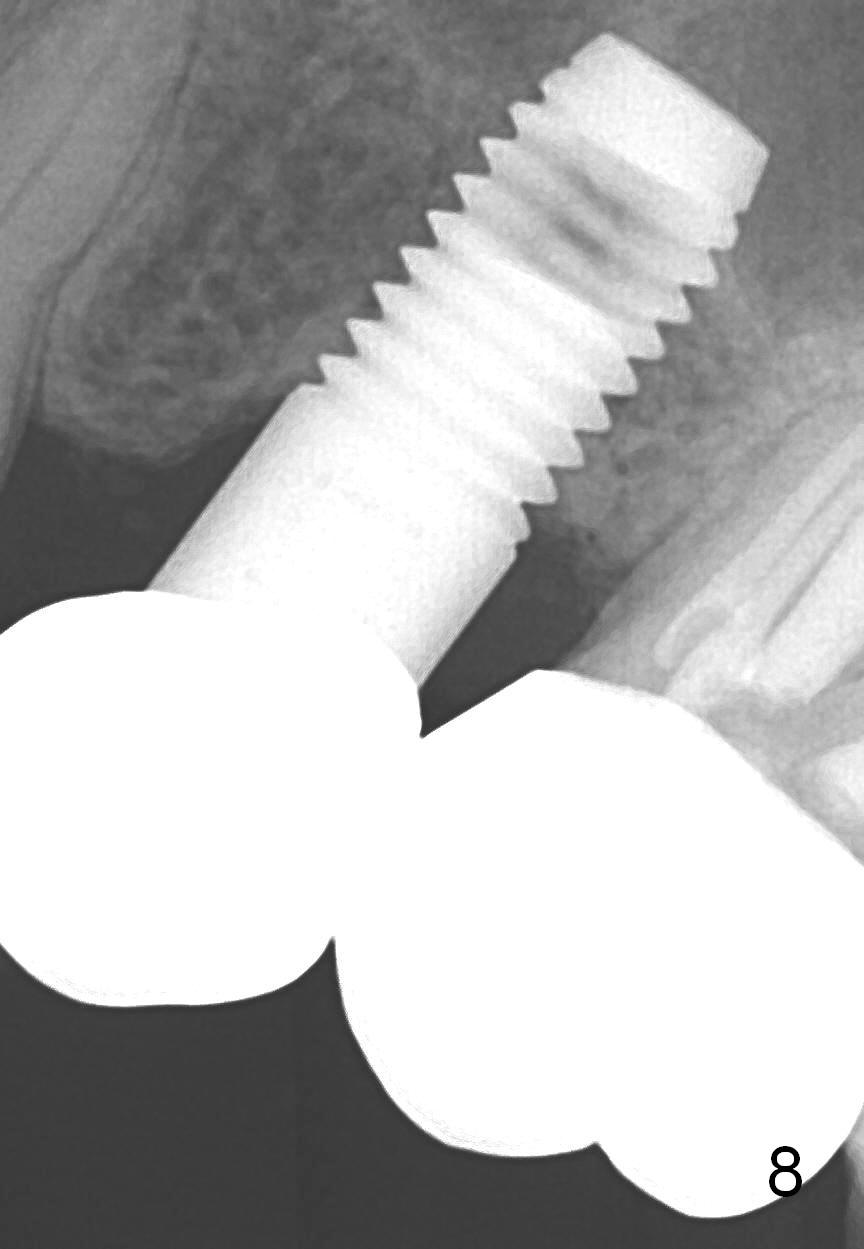

A 59-year-old lady used to have a 3-unit bridge in the upper left quadrant. A 4.5x6mm Bicon implant (Fig.1 B without extruding into the sinus) was placed in the atrophic pontic area 5 months earlier. When the abutment (A) was removed, the implant came out. The osteotomy was processed with a 4.5x14 mm tapered tap, which was unstable. When a 4.8 mm cylindrical tap was placed (past the sinus floor), it was tight (Fig.2). A 5x14 mm cylindrical implant (Fig.3 I) was inserted with elevation of the apparent sinus floor (>, no allograft used in case of sinus infection). Seven months postop, the density of sinus floor increases (Fig.4 <). The implant is stable and processed for crown (Fig.5 C, different view of the lifted sinus floor (<)). While sinus floor density is decreasing, the mesial and distal bone density is increasing 6 months (Fig.6), 1 year 6 months (Fig.7) and 3 year 6 months (Fig.8) post cementation.

It appears necessary to engage an implant into the sinus floor for primary stability for a skinny, probably osteoporotic female patient. The shape and diameter of the implant are also critical.